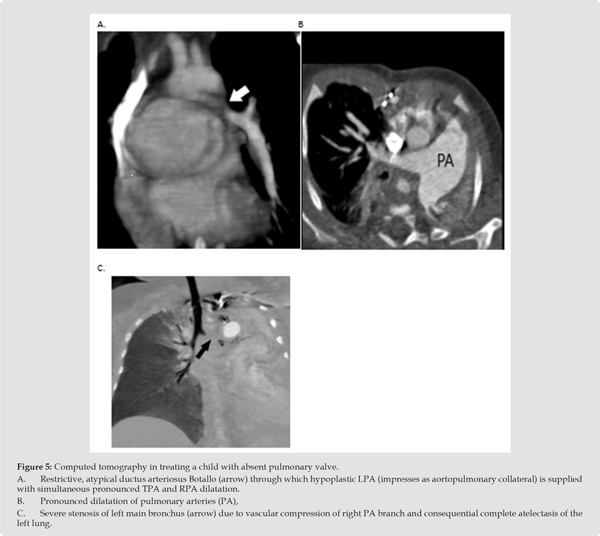

Among the imaging methods that help to clarify the specific anatomical changes and relationships, as well as the evolution of this anomaly, computed tomography stands out. However, imaging alone may be insufficient without other clinical symptoms and imaging studies. For example, restrictive and atypical DB may appear in an isolated view as an aortopulmonary collateral (Figure 5A, patient 2), while in this case it is an atypical, restrictive DB through which a hypoplastic LPA (which is not connected to other parts of the pulmonary tree) is supplied. Some images clearly show marked dilatation of the trunk and pulmonary arteries (right and/or left branches), and their possible progression (Figure 5B, patient 4). The progression is consistent with the development of the clinical picture, i.e. with obstruction of the left bronchus due to dilatation of the TPA or RPA. Timely imaging allows for a decision on the most urgent cardiosurgical intervention, as complete bronchial obstruction leads to atelectasis of the left lung and possible irreversibility of the condition from which recovery is very difficult (Figure 5C & D). MSCT imaging can be supplemented with bronchoscopy.